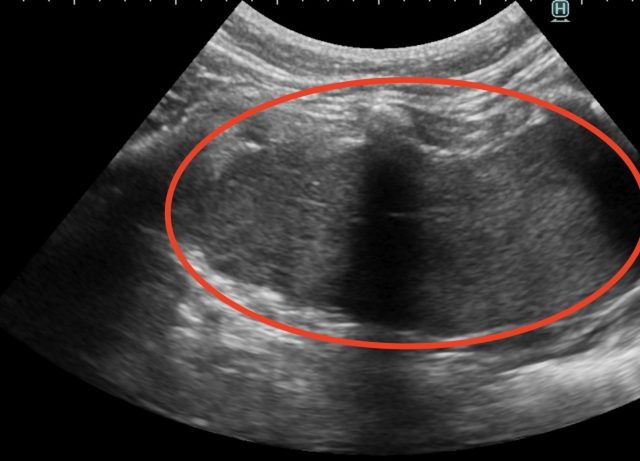

・超音波検査:大きさや広がりの評価

胸腺腫の超音波画像(赤丸)